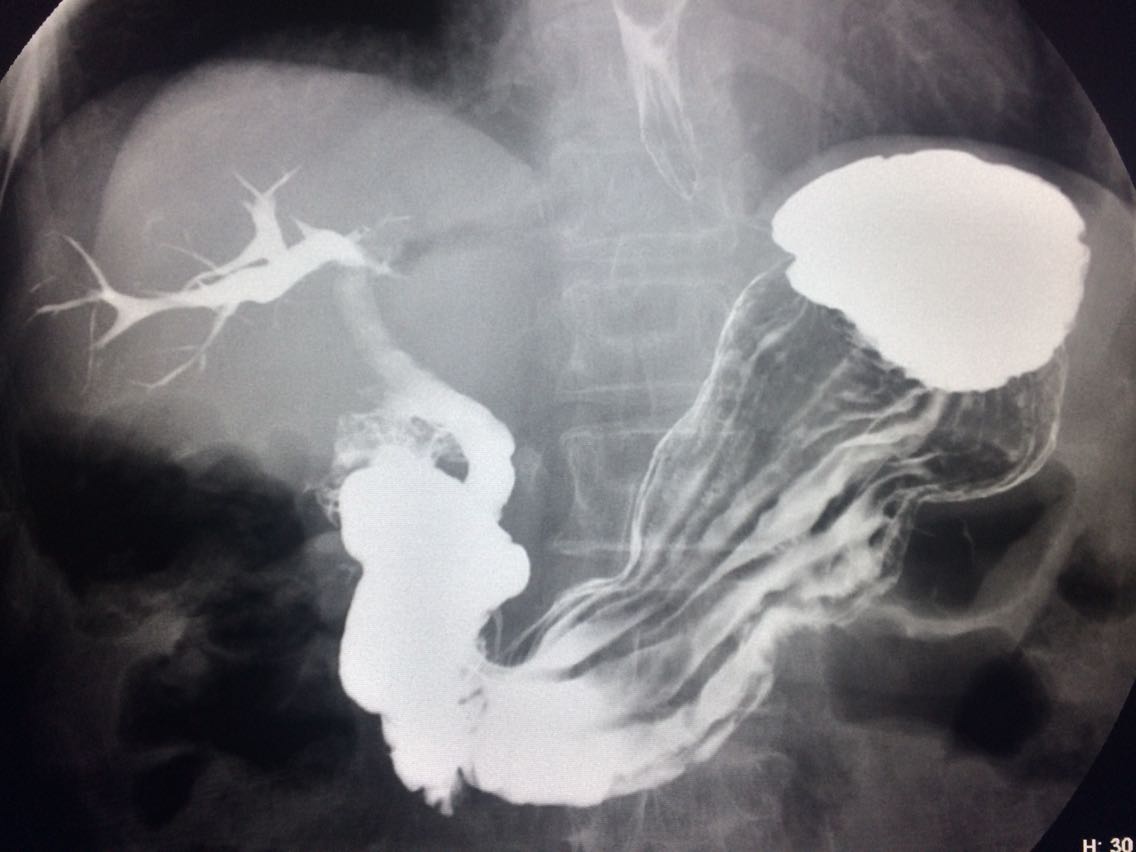

查体未见明显异常。 上消化道造影如图。

诊断食管癌。 造影剂逆流入胆道。